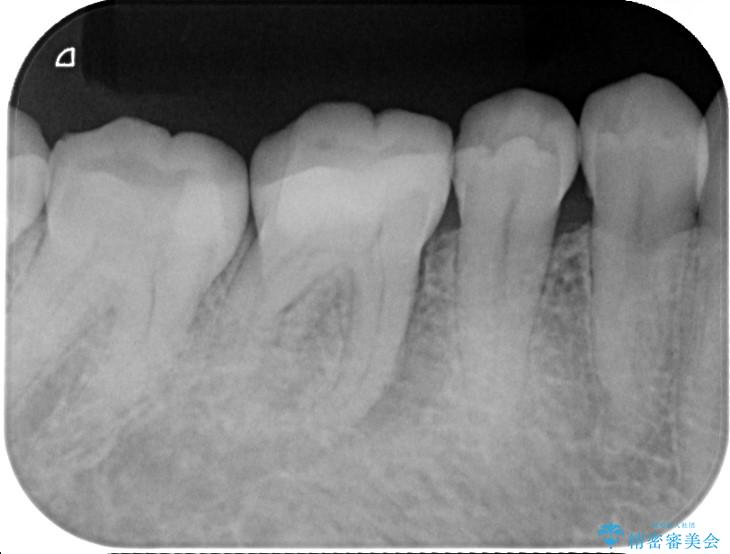

精密検査の結果、根の先に大きな病変が認められますが、根管内が狭窄し湾曲しているため、非常に難易度の高いケースです。

通常の治療器具では奥まで届かず、そのままでは再発や抜歯になるリスクが高いため、マイクロスコープを使用して根の奥まで精密に清掃・殺菌し、歯を残すための治療計画を立てました。